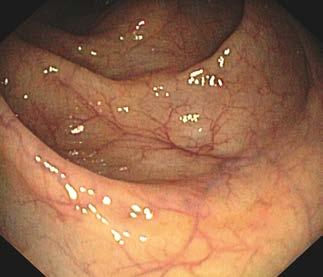

Prawidłowa błona śluzowa jelita grubego jest gładka, lśniąca, z widocznym rysunkiem naczyniowym (ryc. III.B.4-33)

Choroby układu pokarmowego Ryc. III.B.4-33 Kolonoskopia. Prawidłowa błona śluzowa jelita gru bego – gładka, lśniąca, z widocznym rysunkiem naczyniowy m Ryc. III.B.4-34 Kolonoskopia. Prawidłowa kątnica; widoczna zastaw ka krętniczo ‑kątnicza (strzałka) i typowy układ fałdów